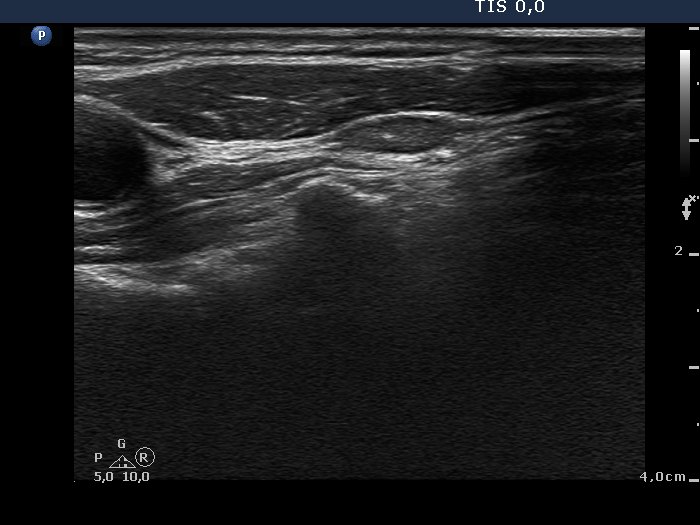

Lymph nodes - case conp 008 (ultrasonographic picture 6)

Lateral to the left lobe, longitudinal scan.